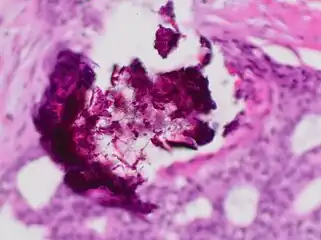

Dystrophic calcification (DC) is the calcification occurring in degenerated or necrotic tissue, as in hyalinized scars, degenerated foci in leiomyomas, and caseous nodules. This occurs as a reaction to tissue damage,[1] including as a consequence of medical device implantation. Dystrophic calcification can occur even if the amount of calcium in the blood is not elevated, in contrast to metastatic calcification, which is a consequence of a systemic mineral imbalance, including hypercalcemia and/or hyperphosphatemia, that leads to calcium deposition in healthy tissues.[2] In dystrophic calcification, basophilic calcium salt deposits aggregate, first in the mitochondria, then progressively throughout the cell. These calcifications are an indication of previous microscopic cell injury, occurring in areas of cell necrosis when activated phosphatases bind calcium ions to phospholipids in the membrane.

- Dead parasites like schistosoma eggs may calcify.